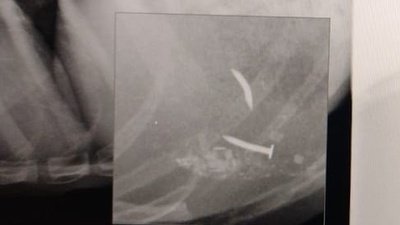

Cabe mencionar dos situaciones días antes habían sacado a unos animales entre ellos un pitbull con clavos en el intestino ya que los hacia comer clavos le arrancó los dientes tenia clavos a un costado del tórax el animal tuvo que ser sacrificado debido a las lesiones. En la mañana antes de la detención del presunto torturador retiro del domicilio otros animales torturados los cuales no se han encontrado. Sus torturas incluían criar gatos perros patearlos quemarlos clavarlos robar mascotas perros gatos y otros clavarlos en los huesos etc, los vecinos se dieron cuenta por los alaridos de los animales torturados, es un peligro para la sociedad cuenta con familiares en la política hecho por el cual ha podido salir sin complicaciones de las anteriores denuncias pero no vamos a permitir más abuso animal recordemos que los asesinos seriales empiezan con estos actos psicopatas apoyen la firma por favor